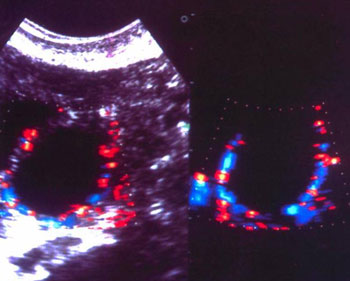

Η αιματική αυτή ροή εξασφαλίζεται μέσω μικρών αγγείων, τα οποία πορεύονται κατά

μήκος της εσωτερικής επιφάνειας της θήκης του ωοθυλακίου(2) (εικόνες 1, 2).

Εικόνα 1. Νεόπλαστα αγγεία

στο τοίχωμα ωοθυλακίου.